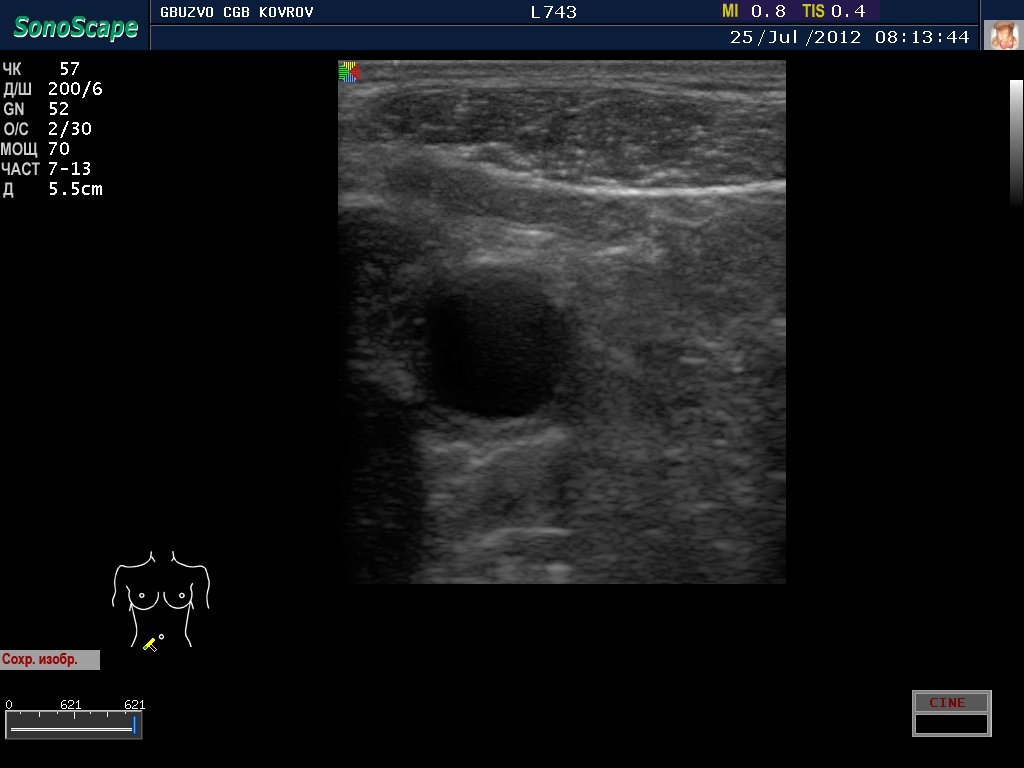

Пациент с жалобами на боли в животе...

jul252012081644.jpg

jul252012081644.jpg [ 202.73 KiB | Просмотров: 23704 ]

Что это такое? Кишка?

ну, скажем так, часть кишечника :D

поподробнее? :shock: бодимаркер находится в правой подвсздошной области, я бы подумал про аппендикс 8-)